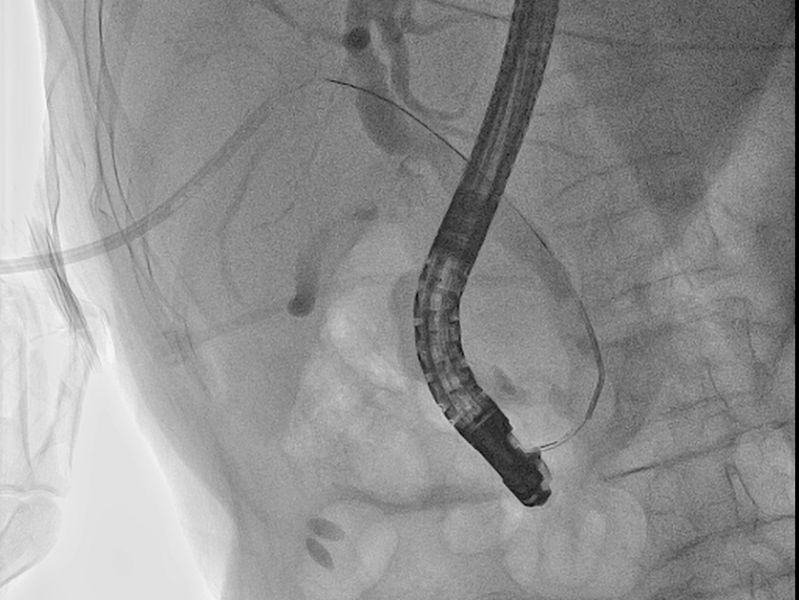

1月14日,在介入科、麻醉科多学科协助下,介入科丁文金副主任医师经PTCD管植入导丝及鞘管至十二指肠乳头开口处,消化内二科向仍运医师在十二指肠镜直视下插入导丝至PTCD鞘管成功会师,从而进入胆总管,切开十二指肠乳头,网篮取净胆总管结石,手术成功,拔除PTCD管。术后常规抗炎及支持治疗,患者康复顺利,于1月23日痊愈出院。

从PTCD管植入导丝及鞘管